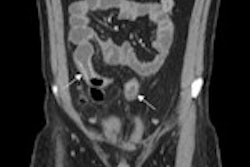

Researchers from the Mayo Clinic College of Medicine in Rochester, MN, found that MR enterography performs as well in children as it does in adults. MR enterography was able to accurately identify inflammation 80% of the time in the terminal ileum, 79% of the time in the right colon, and 90% of the time in the left colon. The number of patients who suffered side effects was low, with two patients experiencing nausea and one fainting, but no ongoing care was required (AJR, September 2012, Vol. 199:3, pp. W367-375).

The research is the largest North American study of its kind and included 70 pediatric patients who underwent MR enterography to review the quality of the images and determine if pediatric patients could tolerate the examination.

While MR enterography does not require any radiation, patients must drink an oral contrast agent, hold their breath at times, and limit their motion during the examination, which can be difficult for pediatric patients.

The majority of children 9 years and older could complete an MR enterography exam without sedation, study co-author Dr. William Faubion Jr. and colleagues concluded. Younger children could drink a smaller amount of contrast material without negatively affecting MR enterography image quality, they added.